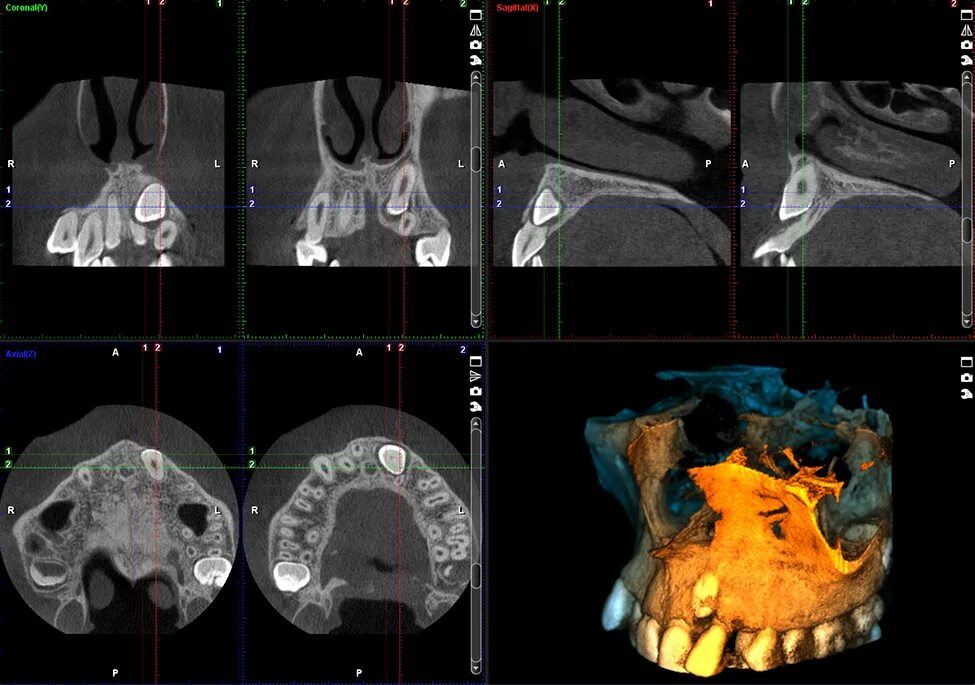

Н 3 кт